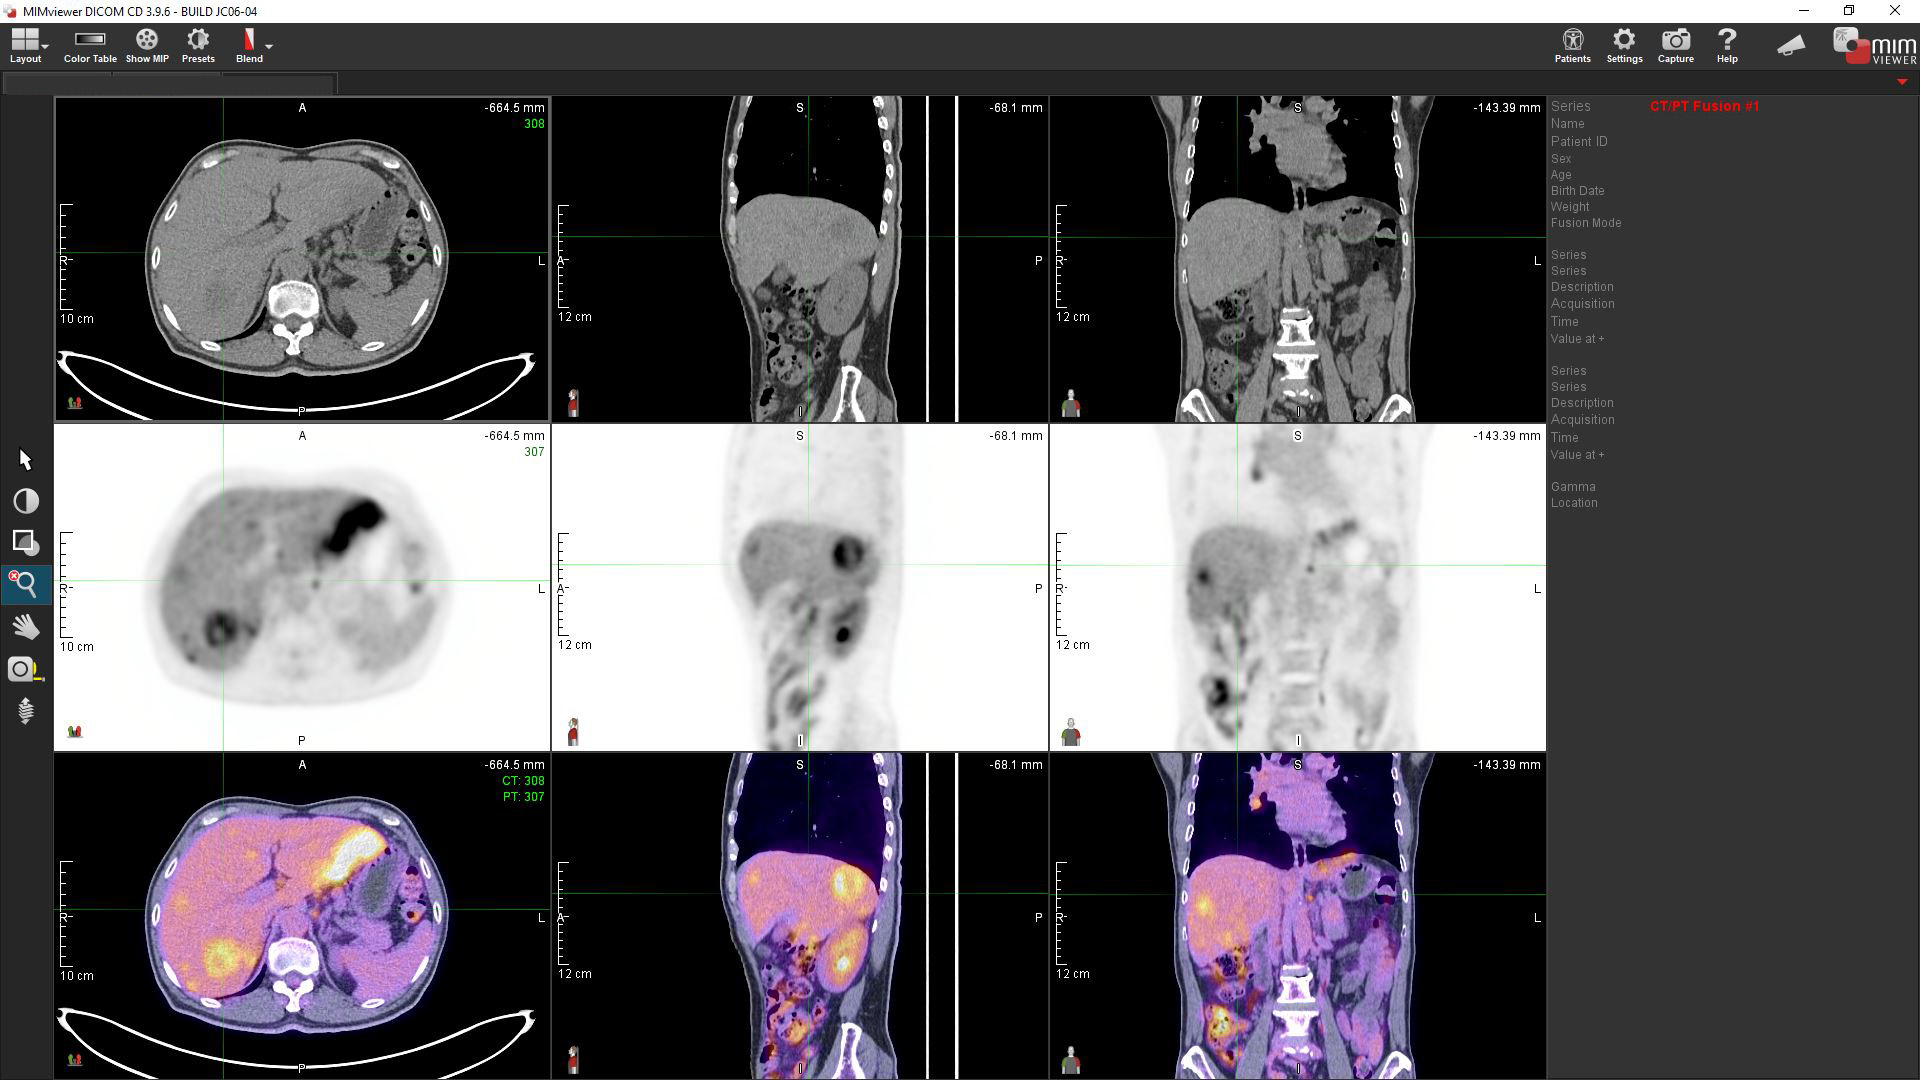

Liver Cancer

Multiple tracers are used to differentiate biochemical properties of liver lesion – Cancer Associated Fibroblast (Ga-68 FAPI uptake)

[C-11] Acetate and [F-18] FDG for hepatocellular carcinoma cellular differentiation (well and poorly differentiated)